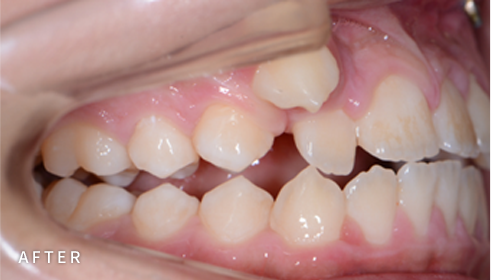

Pediatric and Adolescent Orthodontics

소아청소년교정

아이의 얼굴뼈 성장은 골든타임이 있습니다.

이 시기에 교정을 시작하면, 치아 배열뿐 아니라

턱 성장 방향까지 바르게 유도할 수 있어

성인 교정보다 간단하고 효과적인 결과를 기대할 수 있습니다.

PROGRAM 01

턱 성장교정

성장기에는 턱뼈와 치열의 변화가 활발하기 때문에,

시기를 놓치지 않는 조기 진단과 맞춤 치료가 중요합니다.

단순히 치열교정으로는 얻을 수 없는, 더 효과적인 결과를 기대할 수 있습니다.

치아 배열은 물론, 얼굴의 균형 있는 성장까지 고려해 아이의 바른 성장을 도와드립니다.